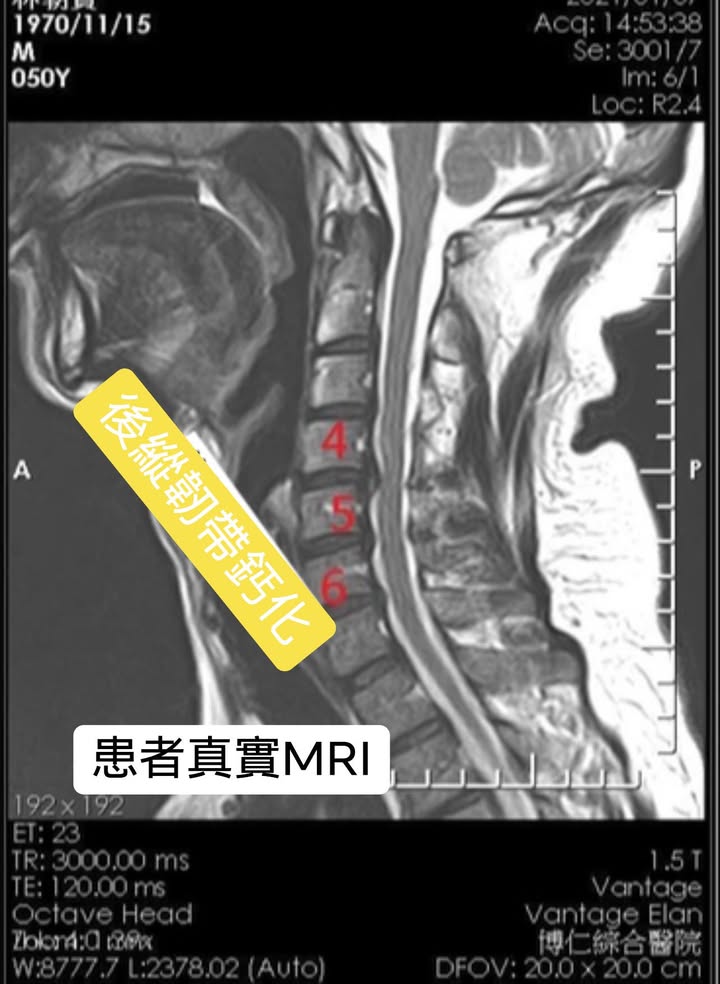

Cervical Spine Treatment Cases 頸椎治療案例 頸椎過直會導致肩膀酸痛嗎?中醫微創針刀療法成功改善頸椎弧度 2021.11.03 頸椎骨刺導致步態不穩、半身麻痛,一定要開刀嗎?中醫針刀治療100天改善實例公開 2021.10.07 冷水刺痛全身、下肢異常竟源自頸椎壓迫?MRI對比揭示非手術療法改善實證 2021.10.08 伏地挺身突然做不到?竟是C6C7頸椎壓迫導致神經肌力減退!中醫微創療法10週改善 2021.09.11 低頭族小心!頸椎滑脫竟導致長期頭痛肩痛與睡眠障礙|12次中醫微創治療成功矯正滑脫 2021.07.16 醫案實證:術後再發的脊髓壓迫症也能靠中醫療法改善 2021.07.10 手術後腳還是麻?頸椎開刀半年症狀未解,靠中醫微創8次改善右腳無力與手麻! 2021.06.30 狂送急診四次竟查不出病因!胸悶心悸原來是頸椎壓迫,靠針刀微創13次改善 2021.06.09 後縱韌帶鈣化壓迫脊髓!步態不穩、手腳麻木竟可逆轉?14週22次針刀治療真實見證 2021.05.06 什麼是中樞型脊髓型頸椎病?症狀、診斷與治療全解析 2021.05.28 神經根型頸椎病症狀解析:肩麻、手痛與肌肉萎縮 2021.04.16 嚴重心悸胸悶竟是頸椎問題!交感神經型頸椎病針治2次症狀明顯改善|真實病例與患者疼... 2021.04.07 從心悸胸悶到手麻夜痛難眠,她竟是頸椎壓迫!真實MRI對比見證中醫逆轉勝療效 2021.04.04 從手腳無力到步態不穩,他竟是頸椎脊髓型壓迫!三個月密集針刀療法逆轉勝|台北蔡大哥... 2021.03.31 頸椎椎間盤突出要一次動四節嗎?手術vs.保守治療完整解析 2021.03.27 ← 上一頁 2 3 4 5 6 下一頁 →